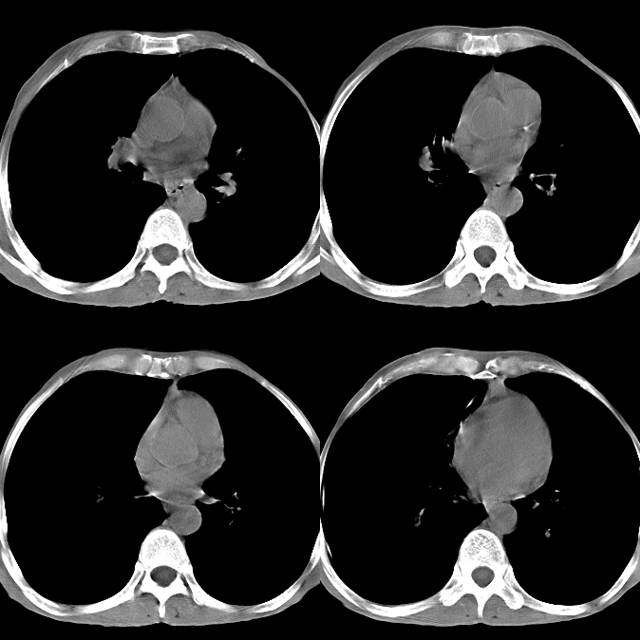

以下是引用心路寻觅在2010-4-17 18:35:00的发言:[br]纵膈多组淋巴结肿大呈“冰冻纵膈”,左肺上叶空洞伴其内结节密度影,考虑淋巴瘤伴左肺上叶曲霉菌感染。[br][br][本贴已被 心路寻觅 于 2010-4-17 18:36:23 修改过]

以下是引用zhangzhongshou在2010-4-17 19:32:00的发言:[br]一元论考虑左肺空洞型肺癌并纵隔淋巴结转移可能性大。